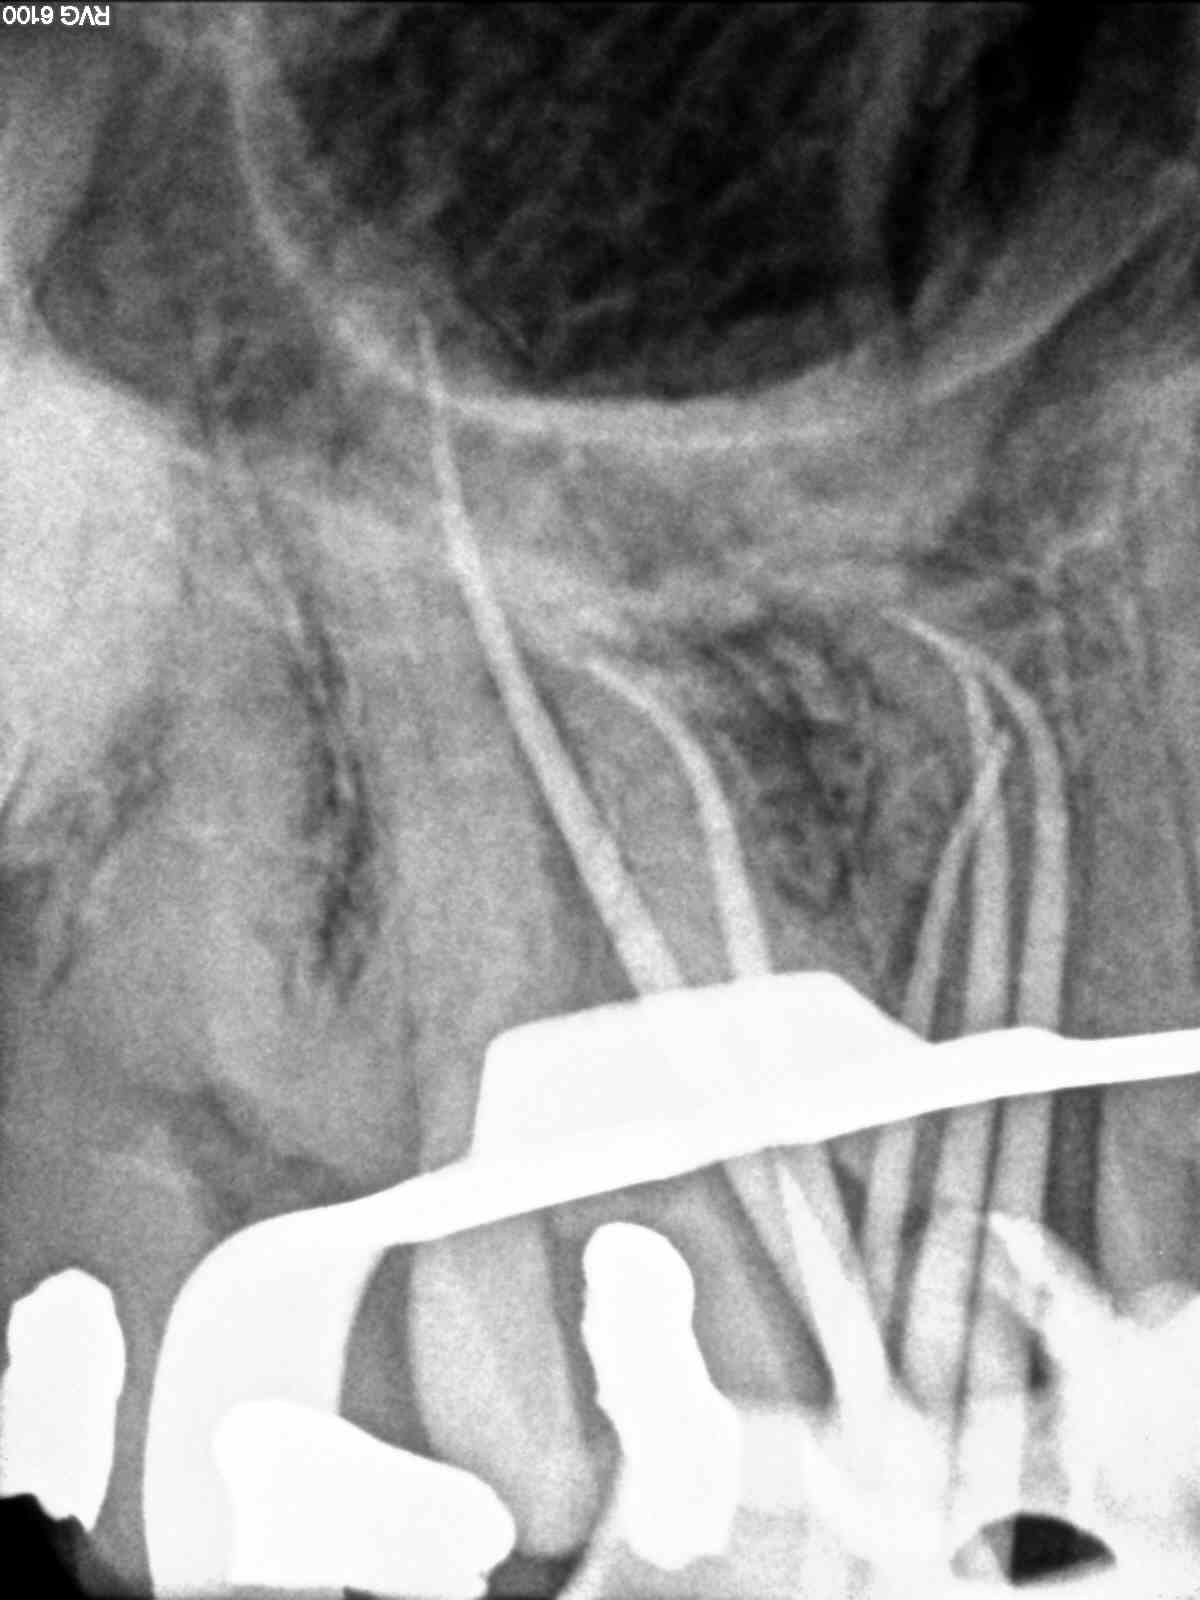

Primeros molares superiores con 3 conductos mesiales

Como todos sabemos, encontrarnos dos conductos en la raíz mesiovestibular de un primer molar superior, cada vez es más frecuente, no por que antes no existiesen, sino por que cada vez somos más conscientes de su existencia,de la anatomía del sistema de conductos tan complicada que puede alojarse en esta raíz, con lo que buscamos ese cuarto conducto. Partamos de la base , que si los buscamos podremos localizarlos, pero hay veces que la cosa se pone algo más complicado, cuando, podemos apreciar un conducto más, quizás se trate de un istmo prolongado del cuarto conducto, pero que en cualquier caso debemos desbridar , limpiar y obturar, con lo que debemos tratarlo como otro conducto.

(un molar superior con tres conductos mesiales)